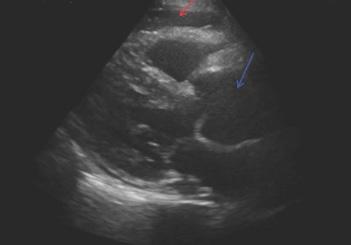

379 RUSH to the Diagnosis: Identifying Occult Pathology in Hypotensive Patients

M Berger, J Hussain, M Anshien

384 Point-of-care Ultrasound Used in the Diagnosis of Reverse Takotsubo Cardiomyopathy P Dave, A Daecher, C Abramoff

Onphysicalexamination,thepatienthadanoral temperatureof99° Fahrenheit(37.2° Celsius),tachycardiaof 108beatsperminute,bloodpressureof106/71millimetersof mercury,97%oxygensaturationonroomair,andadiffusely tenderabdomenwithvoluntaryguardingandrebound tendernesssuggestiveofperitonitis.APOCUSwas performedtoassessforintraperitonealfree fluid.Itrevealeda complexcollectionof fluidwithinternalechoesinthe hepatorenalspaceraisingconcernforaloculatedinfection (See Image and Video).

Abdomino-pelvicPOCUSmayguidetriage,diagnosis, andmanagement,assistingtheclinicianininvestigatinga rangeofdiseaseentitiesincludingbiliarypathology, abdominalaorticaneurysm,orTOA.3–5 Bedsideultrasound isgenerallyreadilyavailableintheEDsettingandmayserve asanadditionalmodalitytoidentifyunusual findingsearlyin thepatient’sclinicalcourse.Itdoesnotrequireionizing radiationandisnottimeintensivetoperform.Cliniciansmay considerearlyuseofPOCUSforperitoneal findings,as evidencedinthiscasepresentation.Inconjunctionwith informationobtainedonhistoryandphysicalexamination, theunusual,rightupperquadrantPOCUS findingsof intraperitoneal fluidwithloculationscausedconcernfora disseminatedpelvicinfection.Thiswasconfirmedasa rupturedTOAwithamoderateamountofpurulent, intraperitonealfree fluidontheoperativereport.Fitz-HughCurtissyndromewasaconcerngiventhecomplicated fluidvisualizedwithPOCUS,buttherewasnocommentof violin-stringadhesions,adhesions,or fibrousadhesions betweentheanteriorhepaticcapsuleandparietal peritoneumnotedonthelaparoscopicoperativereport, althoughitisunknownwhetherthisanatomicarea wasevaluated.

GroupAstreptococcusisararecauseofpelvic in fl ammatorydisease,usuallyseenintheperipartum period,inpatientswithanIUDorwhohavehadother recent,invasivegynecologicprocedures.Inapatientnot respondingtoantibioticsadministeredfortypicalPID coverage,GASshouldbeconsideredasapossibleetiology andapenicillin-basedantibioticadministeredtoprevent progressiontotubo-ovarianabscessformation,peritonitis, andsepsis,particularlyincasesofreturningpatients previouslytreatedwithantibiotics.Bedsideultrasound shouldbeperformedinpatientspresentingwithabdominal pain,anduncommon fi ndingsshouldtriggerfurther investigation.Toourknowledge,noothercasesofloculated fl uidinthehepatorenalspaceassociatedwithPIDhave beenreported.

Video. Rightupperquadrantultrasonographyusingcurvilinear probefanningthroughthecoronalplanedemonstratingascitesand septationsinapatientultimatelydiagnosedwithpelvic inflammatorydisease.